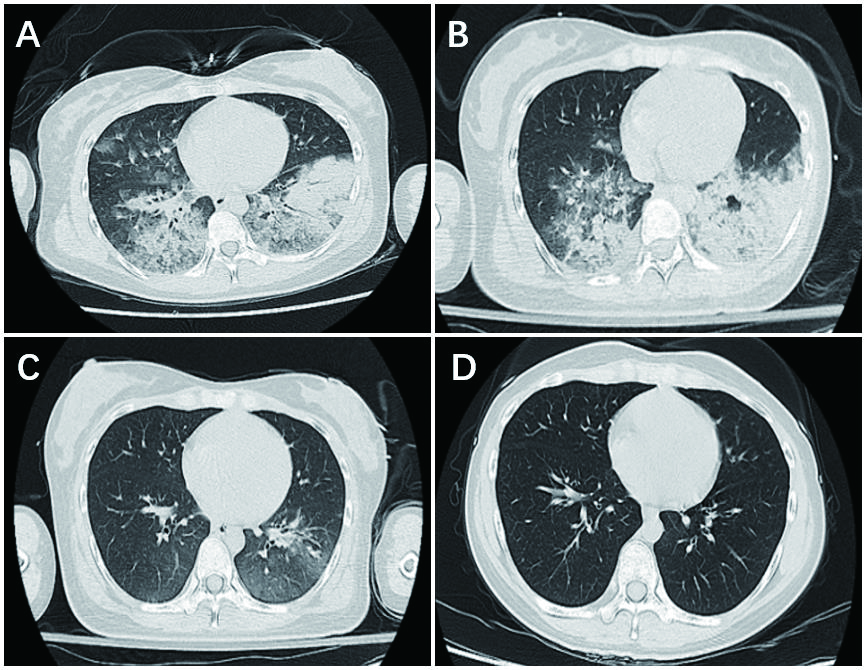

| 图 1 患者的胸部高分辨CT检查。A:入院当天;B:入院后1 d;C:入院后4 d;D:出院后14 d |

患者女,24岁,因“咳嗽4 d,发热2 d,胸闷气急2 h”于2018年6月14日收入急诊科。患者4天前无明显诱因下出现干咳,2天前出现发热,自测体温39℃,至当地诊所就诊,诊断呼吸道感染,在头孢西丁皮试阴性后予头孢西丁钠2 g加入生理盐水250 mL静滴(滴速50滴/min)及布洛芬混悬液15 mL口服后体温下降至正常。6月14日患者起床后感头晕恶心,再次至当地诊所静滴头孢西丁钠,约5 min后患者出现头晕恶心咳嗽等症状加重,伴冷汗,胸闷心悸,呼吸困难,全身无皮疹,测血压未测出,脉搏细弱,考虑注射头孢西丁钠引起过敏性休克,立即停止输液,予肾上腺素2 mg皮下注射后转至本院。入院查体:T 38.5℃, BP 87/53 mmHg(1 mmHg=0.133 kPa),P 122次/min,R 25次/min,血氧饱和度为85%,神志清,面色苍白,双肺可闻及湿啰音。心律齐,未及病理性杂音。腹软,无压痛和反跳痛。双下肢无水肿。辅助检查:急诊血气分析提示pH 7.314,PO2 126 mmHg,PCO2 30.3 mmHg,BE -9.7 mmol/L,SB 16.8 mmol/L,全血乳酸5.6 mmol/L。血白细胞10.6×109/L,中性粒细胞79.2%,嗜酸性粒细胞0.1%。C反应蛋白56.1 mg/L,降钙素原0.336 ng/mL。肌酐91 μmol/L,肌钙蛋白-I 1.106 ng/mL,NT-proBNP 277.95 pg/mL,总IgE 280.6 U/mL,血钾2.5 mmol/L。胸部CT示两肺弥漫渗出伴小叶间隔增厚,左肺下叶局部实变不张(图 1A)。初步诊断:①过敏性休克;②重症肺炎急性呼吸窘迫综合征。立即予储氧面罩吸氧,亚胺培南西司他丁钠、甲泼尼龙静脉应用,去甲肾上腺素维持以及抗组胺补液等治疗,但患者呼吸仍急促,最快50次/min,为进一步治疗收住综合ICU。

入综合ICU后给予患者无创呼吸机辅助通气,继续甲泼尼龙静脉应用,6月15日复查胸部CT示两肺弥漫渗出伴小叶间隔增厚,两肺下叶局部实变不张,较前片(2018-06-14)稍吸收好转。考虑患者肺部感染仍严重,予加用美罗培南及莫西沙星静滴抗感染。但是患者病情无改善,不能平卧,且血肌酸激酶、肌钙蛋白-I和NT-ProBNP均较前升高,心超提示左室节段性运动减弱,左心功能减低,考虑并发急性心肌炎,予气管插管,呼吸机辅助通气。6月18日复查胸部CT示两肺多发炎症,较前片(2018-06-15)明显吸收好转(图 1C)。予停用甲泼尼龙,拔除气管插管,转入感染性疾病科病房继续治疗,予口服莫西沙星治疗1周后出院。出院后2周患者复查胸部CT示右肺中叶少许纤维灶,左下肺少许渗出,较前(2018-06-18)明显吸收(图 1D)。